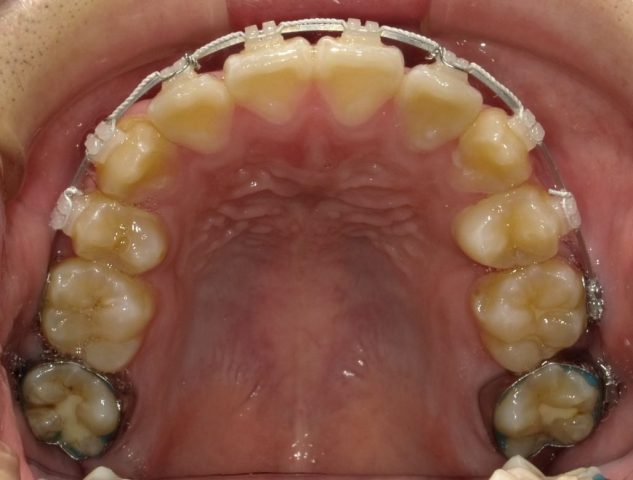

【上顎咬合面観】

2023年1月

永久歯生え揃い、身長の伸びも落ち着いてきたので

2段階目スタートします。

2023年1月(16歳8ヶ月)

顎の大きさに比べ、歯が大きいので抜歯してスタートします。